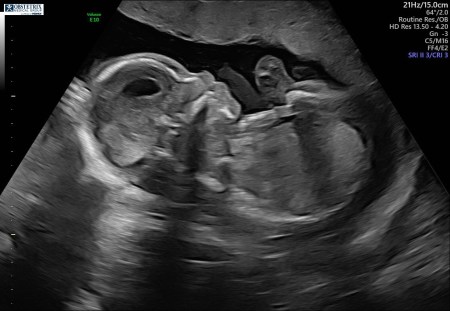

Well, I did it! I officially delivered our second baby girl during a global pandemic. Just like many […]

I know a lot of you are scared and worried about being pregnant during all this madness. I […]